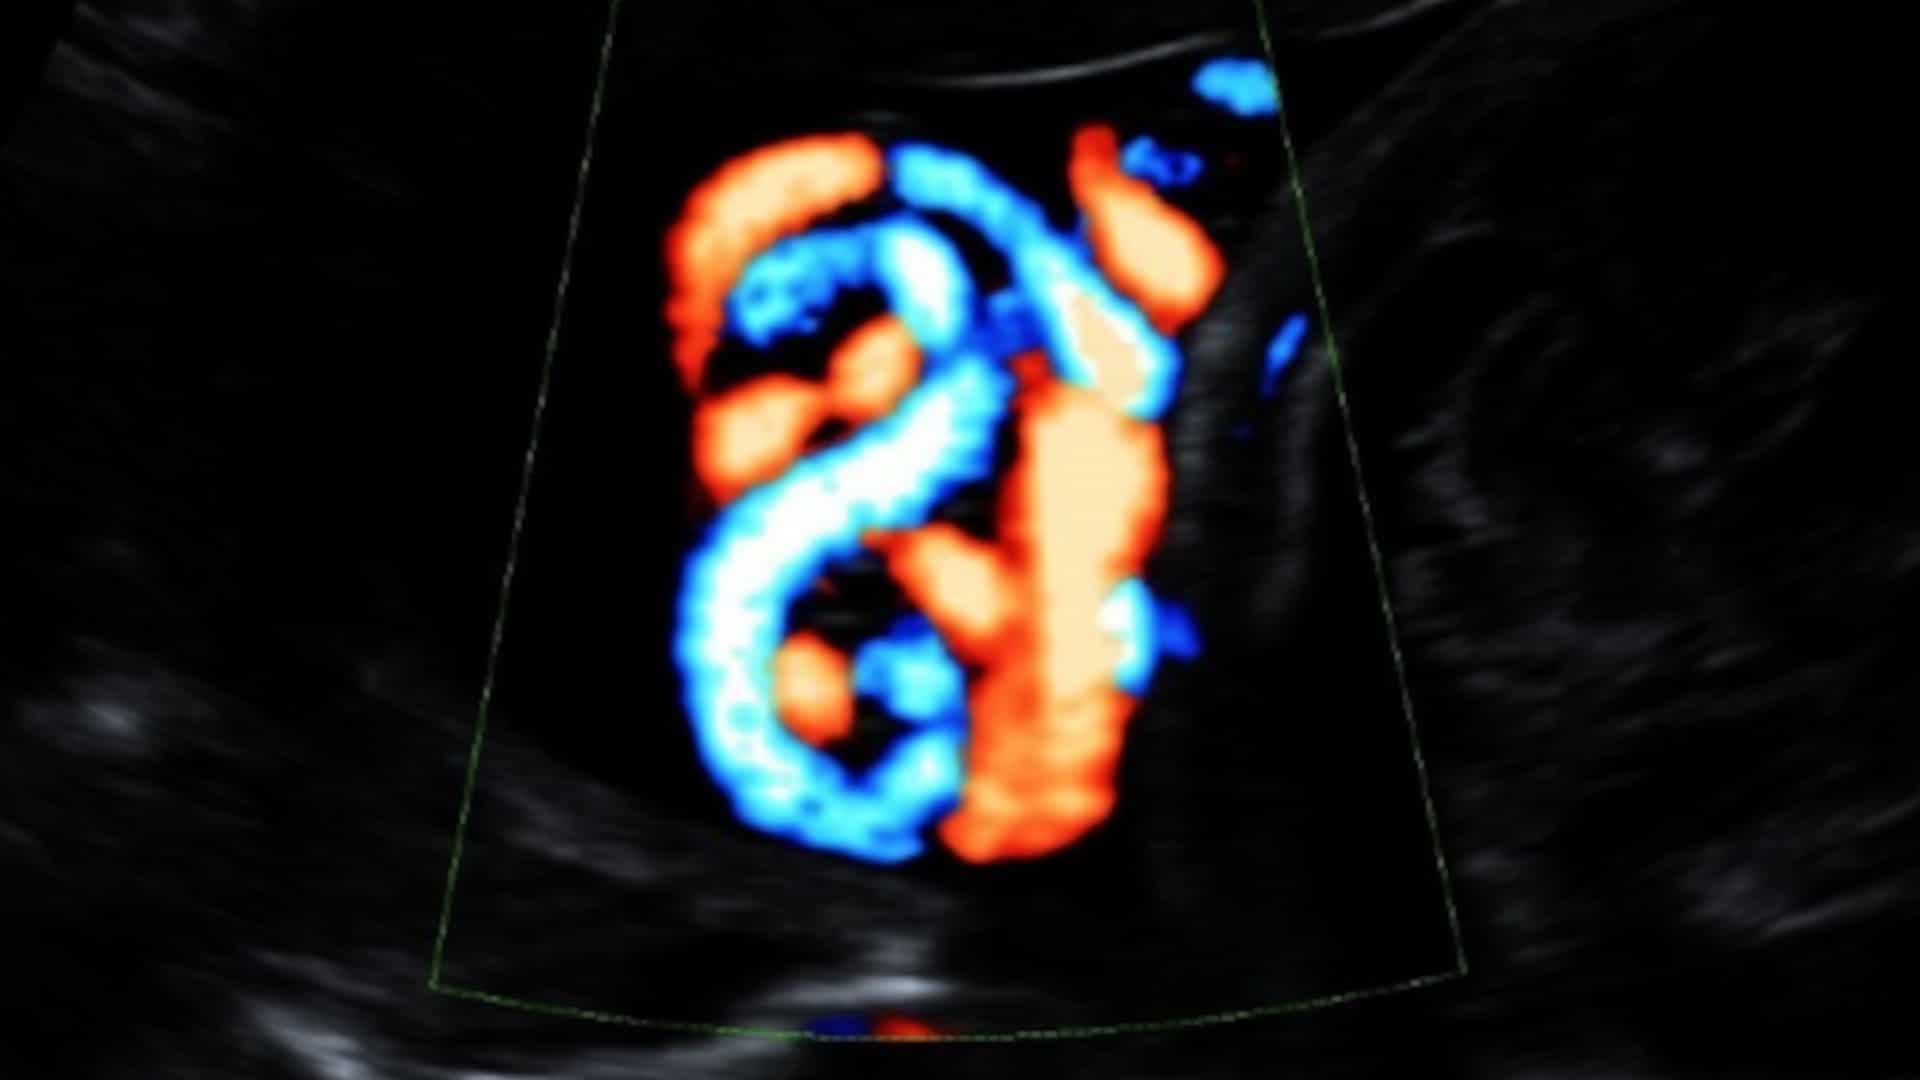

Umbilical cord knot seen on screening images

A true umbilical cord knot can be viewed by an imaging technology called 3D HD Flow. Some OB-GYNs are advocating for this kind of screening with all pregnancies. Bohîlțea et al./Journal of Medicine and Life

Routine prenatal care already typically involves one or two ultrasounds using a two-dimensional Doppler—which shows a flat, two-dimensional image on a screen— to check on fetal growth and health between weeks 18 and 22 of pregnancy. During these screens, most technicians do examine the umbilical cord, although they only look for blood flow and the proper number of cord vessels. Collins’ protocol calls for additional imaging with a 3D or 4D Doppler, which allows a physician to evaluate the nooks and crannies of the fetus and the cord.